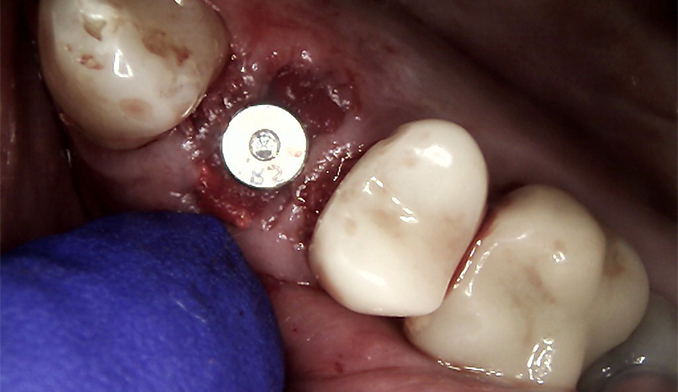

Sinus Lift and Implant Placement for Missing Molar

The patient wished to replace a missing upper left molar. To allow placement of an appropriately sized implant for long-term success, we performed a crestal sinus lift to gently raise the sinus floor. Bone grafting was completed at the same time, and the dental implant was placed in a single procedure to restore the missing tooth.